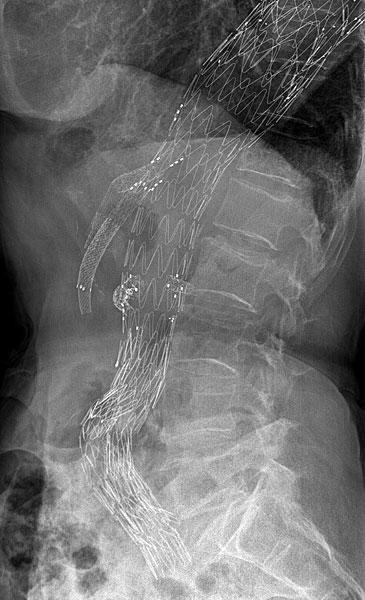

FEVAR utlösta njurgrafter Efter vidgning med CODA-ballong expanderas varje graft efterhand i de olika visceralkärlen.

- Varje visceral-graft efterdilateras efter resp. deponering med PTA ballong 10×20, 80cm (ny PTA-ballong till varje graft) som löper över Storq-ledaren in i resp. sidoartär.

- Innan PTA-ballongen tas ut ska introducerskidan åter ”snytas” in en bit (2-3cm) i den aktuella visceralkärlet inför kontroll med kontrastinjektion.

Kan man ej snyta in introducerskidan får man försöka med att föra på dilatatorn på Flexor-skidan. - Visceralstentgrafterna kontrolleras var för sig efter varje PTA med handinjektion kontrast eller tryckspruta via resp Flexor-introcucer.

- Avslutningsvis kontrolleras den proximala fenestrerade graften och visceralgrafterna med kontrastserie (ca 20ml, 20ml/sek) från den 4F UF kateter som nu kan föras upp en bit kranialt ovanför alla fenestreringar.

FEVAR Bifurkationsgraften föres på plats, över Lunderquist-ledaren, en bit upp i proximal body graftet (≥5,5cm gärna mer), expanderas och deponeras helt.

- Övergången mellan proximala och distala body graftdelarna dilateras därefter med CODA-ballongen.

- Det behövs alltid en benförlängning (iliac leg graft) från bifurkationsgraftens kontrasida för att den ska ligga ner och täta i a.iliaca com.

- När benförlängningar ligger på plats ska skarvarna mellan proximala graften och distala bifurkationsgraften och benförlängningarna dillateras med CODA-ballongen.

- Avslutande serier (ca 20ml, 20ml/sek) körs via lång pigtailkateter (110-130cm) från någondera ljumske.